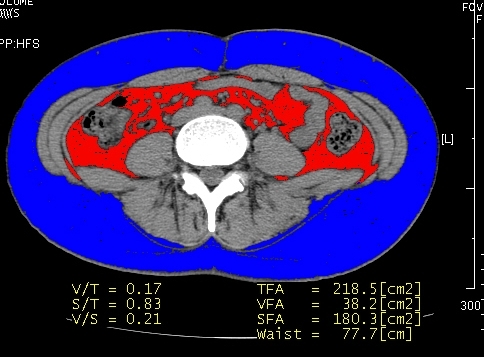

| 복부지방 CT | 내장 지방 평가 |

체지방 분석기계- 체지방률, 근육량을 간편하게 측정할 수 있습니다. | 마른 체형이라도 복부비만일 수 있다!!!복부 (내장)지방 측정 CT각종 성인병을 일으키는 내장지방을 정확히 측정할 수 있습니다. |